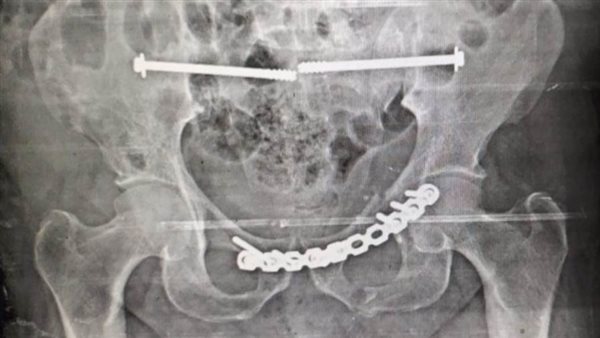

شملت العملية تركيب شرائح ومسامير وتثبيت الحوض من الخلف بالفقرات العجزية باستخدام مسامير مجوفة.